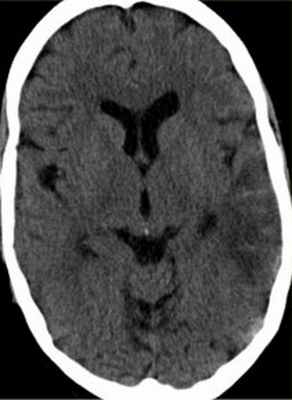

На неконтрастных КТ могут быть видны сгустки крови в тромбированном синусе (“дельта” – симптом), повышенная плотность от синуса (симптом “шнура”). При контрастировании, наоборот наблюдается отсутствие заполнение синуса на ограниченном участке (“обратный дельта” симптом) и отсутствие заполнение синуса контрастом.

МРТ головного мозга. Т2-зависимая МРТ. Двухсторонний венозный инфаркт.

МРТ головного мозга. Аксиальная МРТ типа ДВИ. Двухсторонний венозный инфаркт зрительных бугров.

При МРТ головного мозга хорошо видны последствия тромбозов венозных синусов и корковых вен – венозные инфаркты. При МРТ в СПб мы видим (как в высоком поле, так и на открытом МРТ) , что они отличаются тем, что не связаны с бассейном артериального кровообращения и содержат геморрагический компонент. Тромбоз венозного синуса как неотложное состояние при МРТ СПб должен диагностироваться в специализированном стационаре.